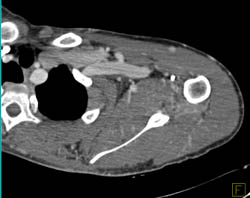

Abscess With Vascular Changes